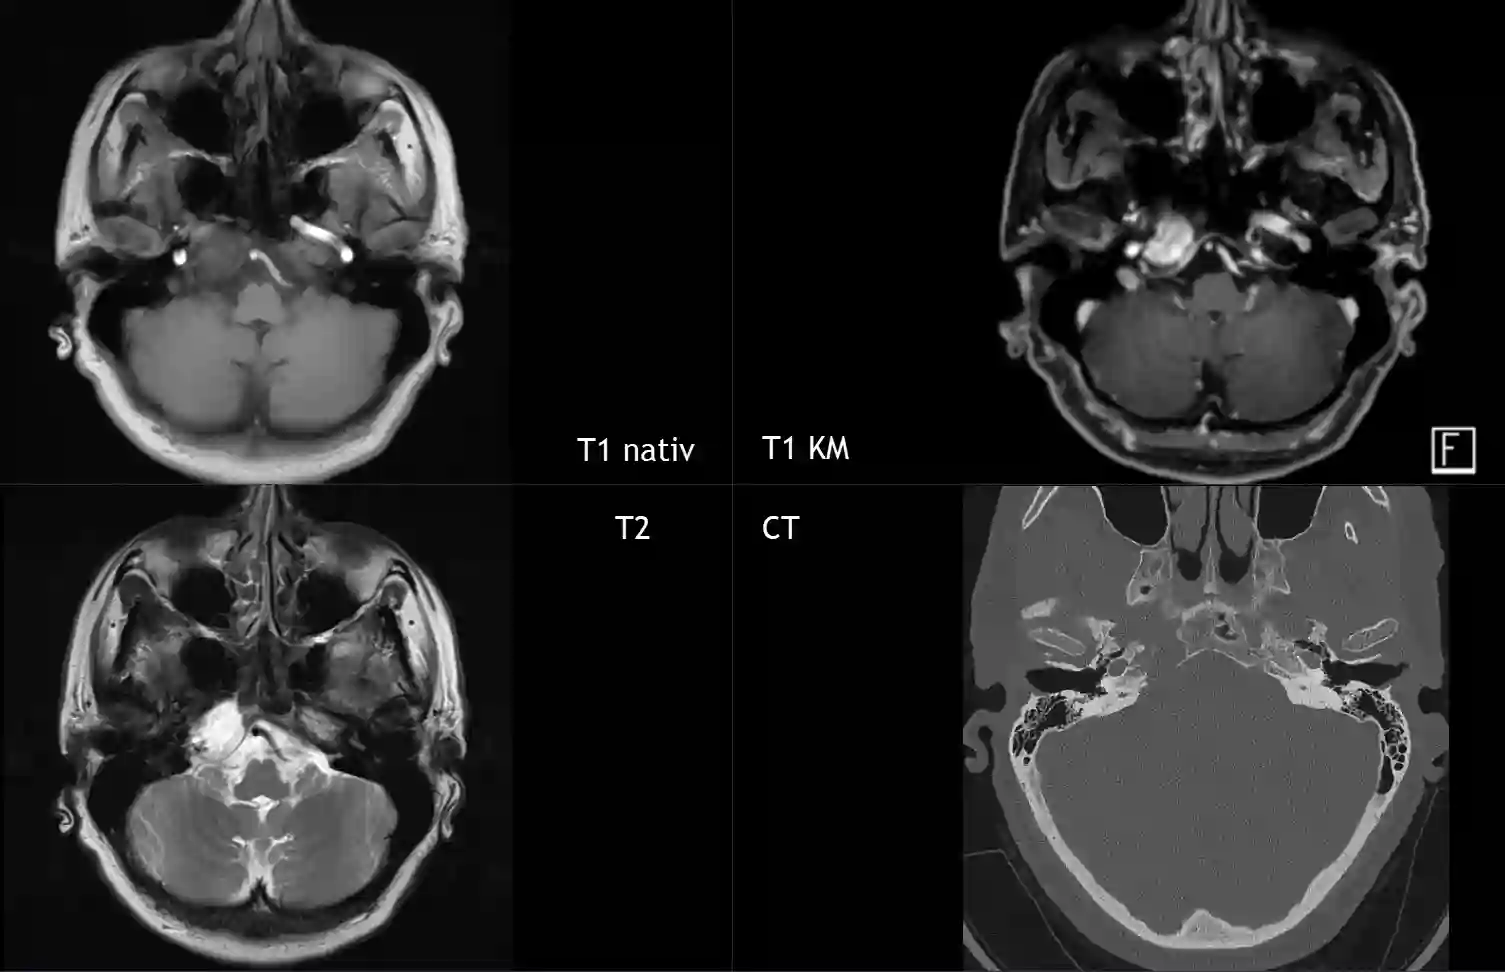

Chondrosarkom im MRI und CT

Intrakranielles Chondrosarkom in verschiedenen MRI Sequenzen und im CT.